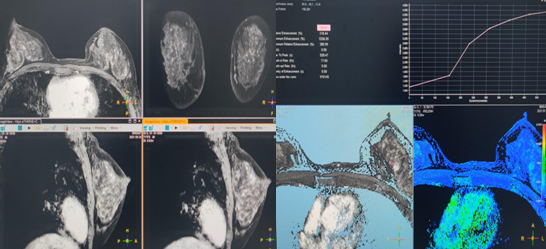

五、乳腺疾病应用

可以进行横轴位、矢状位、冠状位多方位成像,并且具有较高软组织分辨率,可避免因乳腺钼靶图像重叠及超声对非肿块型病变不敏感而造成的病灶遗漏,对于乳腺肿瘤良恶性的诊断具有较高的诊断准确性。

乳腺磁共振成像